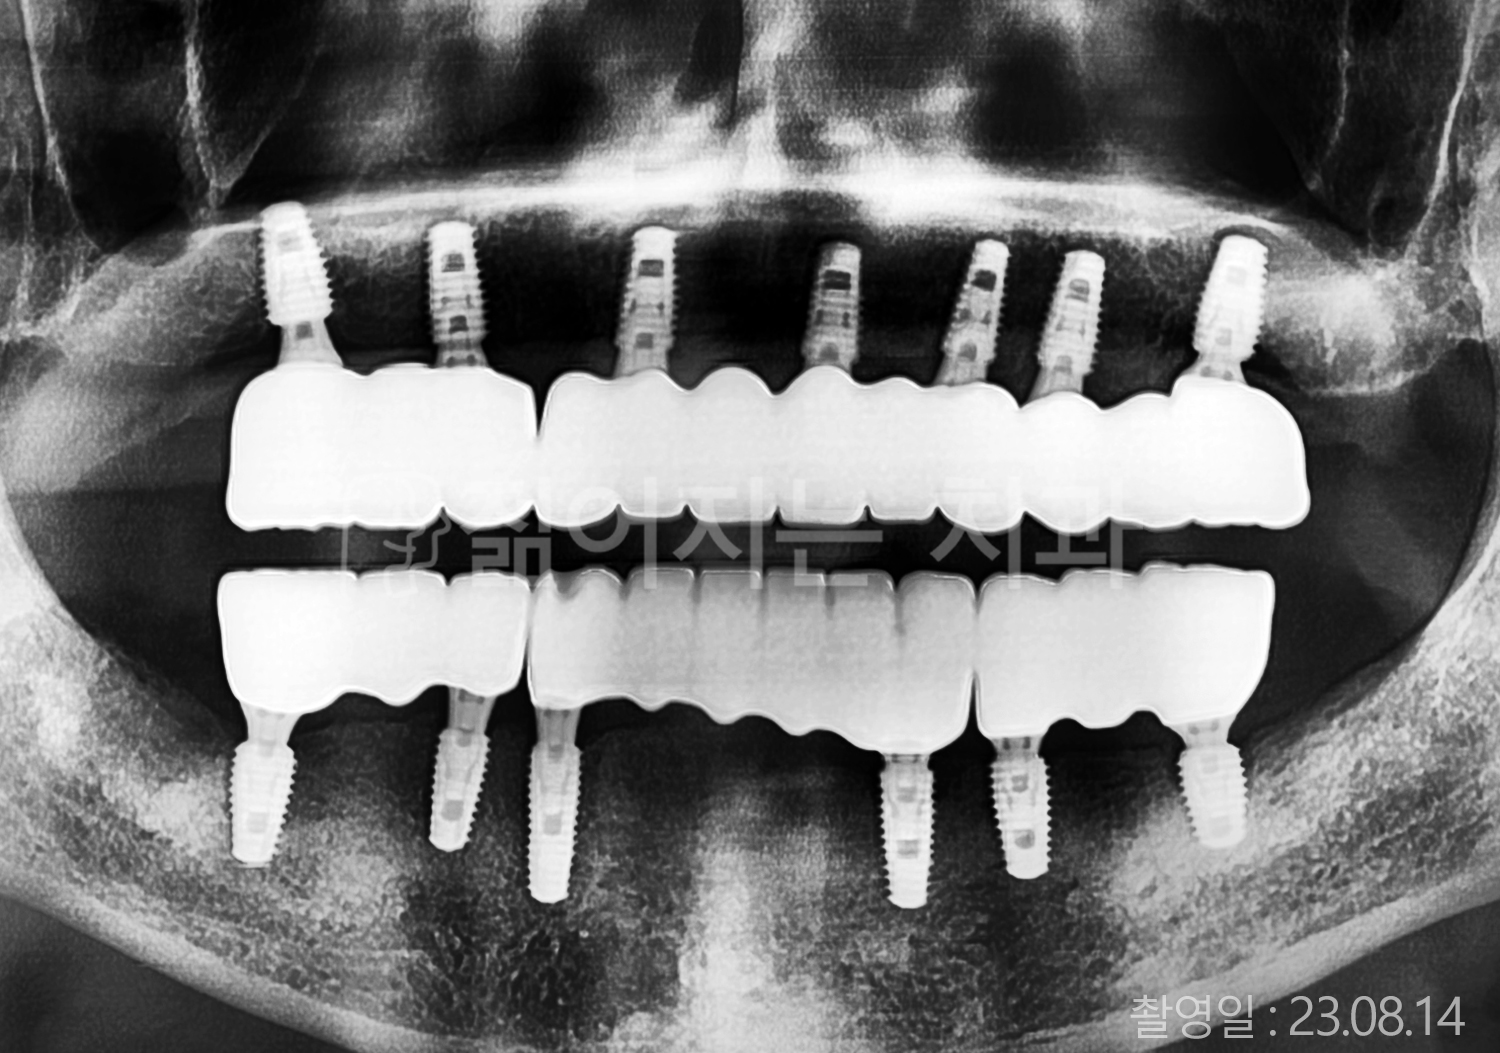

• 40대 전체치아 10개 이상 임플란트

• 50대 전체치아 10개 이상 임플란트